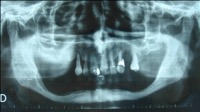

Indications Avant d’envisager une réhabilitation dentaire implanto-portée il faut s’assurer de la présence d’os en quantité et en qualité suffisante. Un examen clinique et radiologique par scanner est nécessaire.

Il faut rechercher également les foyers infectieux et préciser la situation des sinus maxillaire et du nerf mandibulaire (qui traverse la mandibule) avant d’envisager la pose d’implants. En cas d’obstacle anatomique (nerf trop proche, quantité d’os insuffisante…) une chirurgie pré-implantaire doit être programmée. Ainsi des greffes osseuses peuvent être envisagées avant la pose des implants, ou un déroutement des nerfs dentaires.

Photo indication greffe osseuse pré-implantaire